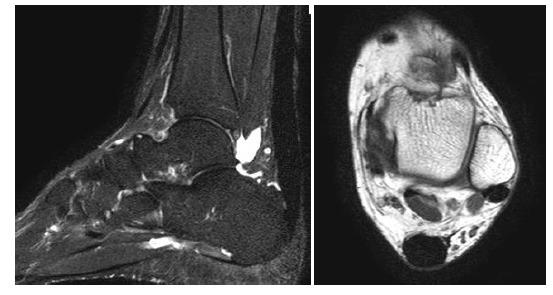

手术修复后跟腱的磁共振成像

MR Imaging of the Achilles Tendon after Surgical Repair.

Achilles tendon tear is common and increasingly frequent. Magnetic resonance imaging (MRI) is the modality of choice for radiological evaluation. It is accurate to assess the status and integrity of the tendon with well documented features. In this article, the MR findings of a normal Achilles tendon as well as common diseases like insertional and noninsertional tendinosis, chronic tendinosis with marked lengthening, tendon rupture are illustrated. After a torn Achilles tendon receives surgical repair, it undergoes different stages of healing process including inflammatory, reparative and remodeling phases. Acute scar tissue in the surgical bed may share similar MR features of tendon re-rupture especially in the early healing phase because both are T2W hyperintense. The size of the gap may even appear larger than expected on T2W images possibly due to tendon remodeling. Understanding of the healing process in post-operative period may prevent overestimation of tendon gap and misdiagnosis of re-tear. We describe the MR features of the post-operative changes with serial studies in different months after surgery. The MR findings with the highlights of the expected sequential changes in normal healing process are illustrated in different cases. A case with surgical repair on a partial tear of Achilles tendon is also included.

摘要